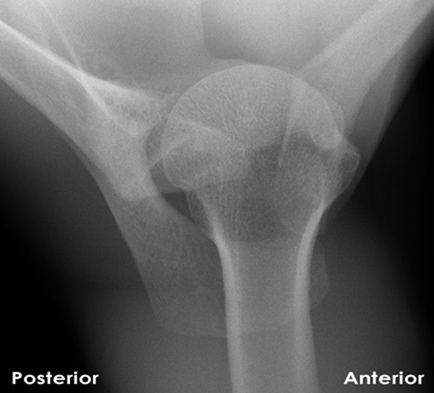

In the acute assessment of a dislocated shoulder, what is the MOST reliable way to differentiate between an anterior and posterior dislocation on a single, well-centered AP radiograph, if other views are unavailable?

Correct Answer: The 'light bulb sign' for posterior dislocation

Explanation:

While several signs can suggest a posterior dislocation on an AP view, the 'light bulb sign' is considered the most reliable. This refers to the appearance of the humeral head as uniformly rounded and internally rotated, obscuring the normal profile of the humeral head (the 'handshake sign' or half-moon sign). Hill-Sachs and Bankart lesions are associated with anterior dislocations. The rim sign (widening of the glenohumeral interval) and trough line sign are also for posterior, but the 'light bulb sign' is a common and distinctive feature on AP. Degree of external rotation is usually lost in posterior, but 'light bulb' describes the specific head shape due to fixed internal rotation.